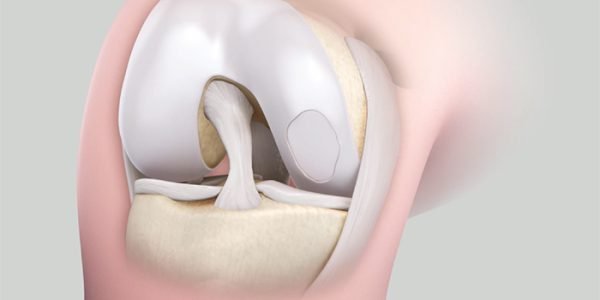

CARTILAGE PROCEDURES

Articular cartilage is a firm, rubbery material that covers the ends of bones in the knee joint.

AUTOLOGOUS CHONDROCYTE IMPLANTATION

Autologous chondrocyte implantation, relies on newly grown cartilage cells.